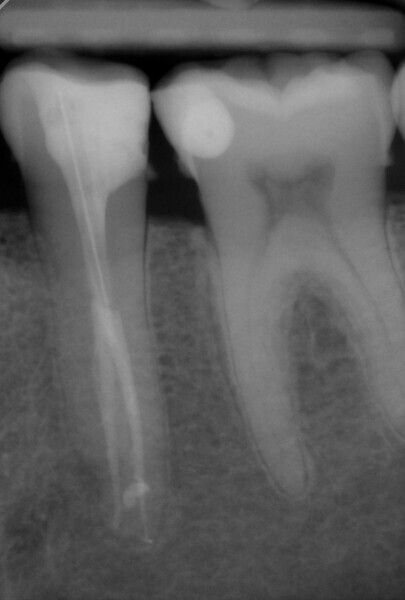

The treatment was performed in two appointments. The first appointment involved preparation, cleaning and interim medication with calcium hydroxide. After applying the dental dam to isolate the working field, the 25/0.12 HyFlex EDM Orifice Opener and the 10/0.05 HyFlex EDM Glidepath files were initially used to open the canal and create the glide path. The actual preparation was performed with 15/0.04 and 20/0.04 HyFlex CM files followed by the 25/~ HyFlex EDM OneFile (Fig. 4). During treatment, the canals were rinsed extensively with CanalPro sodium hypochlorite and EDTA and dried with the corresponding HyFlex paper points and the practical, flexible Surgitip endodontic aspirator tips (COLTENE) before application of the calcium hydroxide dressing (Fig. 5). Ultrasonic activation was also used to enhance the effect of the irrigation solutions.

Obturation and final restoration with a fibre post were performed at the second appointment. The radiograph confirmed that I had been able to treat both root canals along the entire length of the tooth (approximately 23 mm) with minimal loss of tooth structure and in the most conservative manner possible (Fig. 6).